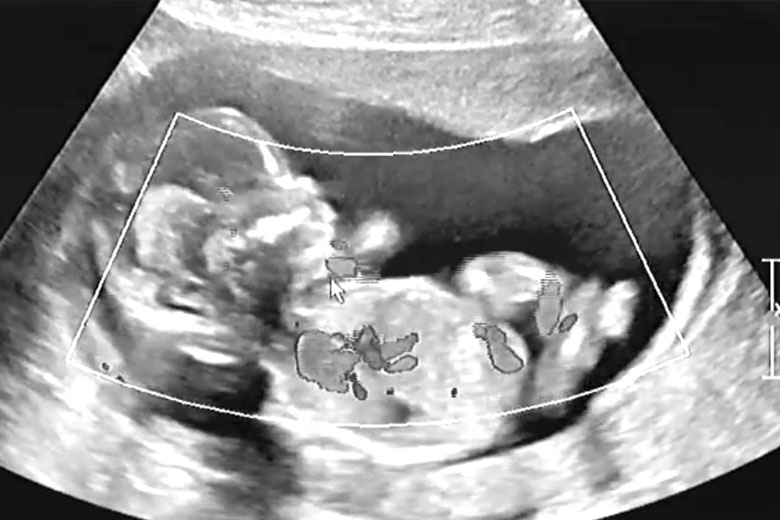

During the delivery, the medical experts did everything they could to make it as natural as possible. This included no scans or tests to check the baby’s health. But once she gave in to the medication and the epidural, she decided to have an ultrasound as well. After all, she had been busy for tens of hours.

The ultrasound showed a perfectly healthy baby. Everything they could see on the screen seemed fine. The little one was fine, and the delivery went well. It wouldn’t be long before Nicole could hold her baby in her arms. Matt had a smile from ear to ear and held his wife’s hand.